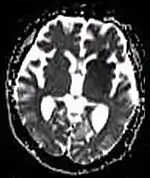

Each tissue returns to its equilibrium state after excitation by the independent relaxation processes of T1 (spin-lattice; that is, magnetization in the same direction as the static magnetic field) and T2 (spin-spin; transverse to the static magnetic field). To create a T1-weighted image, magnetization is allowed to recover before measuring the MR signal by changing the repetition time (TR). This image weighting is useful for assessing the cerebral cortex, identifying fatty tissue, characterizing focal liver lesions, and in general, obtaining morphological information, as well as for post-contrast imaging. To create a T2-weighted image, magnetization is allowed to decay before measuring the MR signal by changing the echo time (TE). This image weighting is useful for detecting edema and inflammation, revealing white matter lesions, and assessing zonal anatomy in the prostate and uterus.

The standard display of MRI images is to represent fluid characteristics in black and white images, where different tissues turn out as follows: